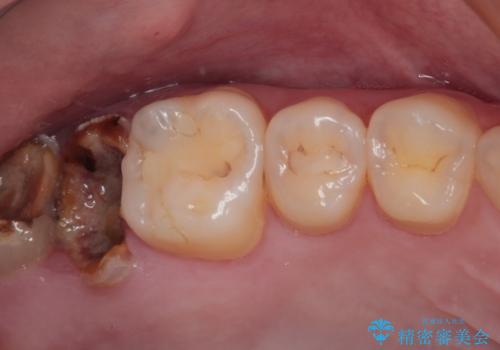

放置したむし歯 抜歯後にインプラントで補綴治療

銀歯をなくしたい 全顎的なむし歯治療